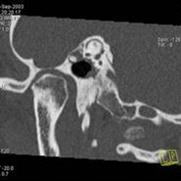

намного сокращается. Например, КТ легких проводится за 20-30 секунд. Рис. 6 на

примере исследования пирамиды височной кости иллюстрирует принцип копьютерной

томографии высокого разрешения. Применены тонкие срезы (0.5 мм) и

"острый" алгоритм реконструкции (кернель 90). (Слева) отчетливо видны

элементы внутреннего уха - улитка, полукружные канальцы. (В центре) показана

проекция продольного сечения височно-нижнечелюстного сустава. (Справа) -

холестеатома.

Рисунок6 -Принципы компьютерной

томографии высокого разрешения (КТВР) на примере исследования пирамиды височной

кости.